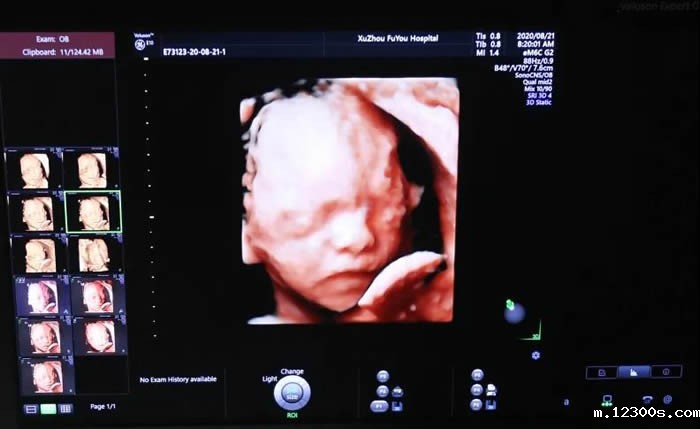

张丽主任介绍,无论是三维还是四维,都是在二维超声的基础上,利用计算机再处理技术达到立体模式重建的超声诊断技术,能看到胎儿的立体图形。“也就是说,三维彩超好比照相机,能捕捉胎儿立体静态的画面,四维彩超就像摄像机,可以看到实时动态的胎儿画面,比如:打呵欠、手舞足蹈的过程。”

需要强调的是,四维彩超不是万能的。对于胎儿身体内的各项器官异常和隐藏结构,是检查不出来的,像手指、脚趾,很容易因并拢而无法看出是否有异常。所以准妈妈不要认为四维彩超能排查所有畸形。

张主任还有些无奈的提到,有些孕妇一进诊室就会询问,仪器是不是某品牌的?是标清还是高清?就像被商业广告洗脑一样,导致大家的关注点集中在了宝宝的肢体动作、颜面部录像上。

“这是一个很大的误区。超声科医生要做的是在胎儿结构筛查清楚的前提下,拥有一张清楚的面部画面,这是最完美的。但是,不建议为了捕捉胎儿的一个动作、某个画面反复长时间使用。”